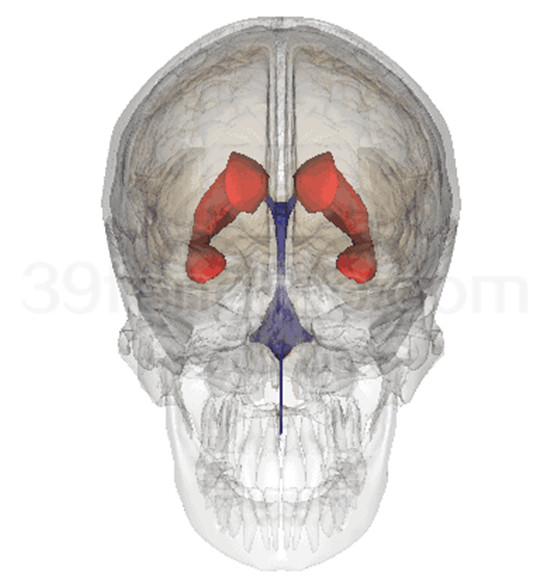

中枢部分包括脑和脊髓,分别位于颅腔和椎管内,两者在结构和功能上紧密联系,组成中枢神经系统。

脑部